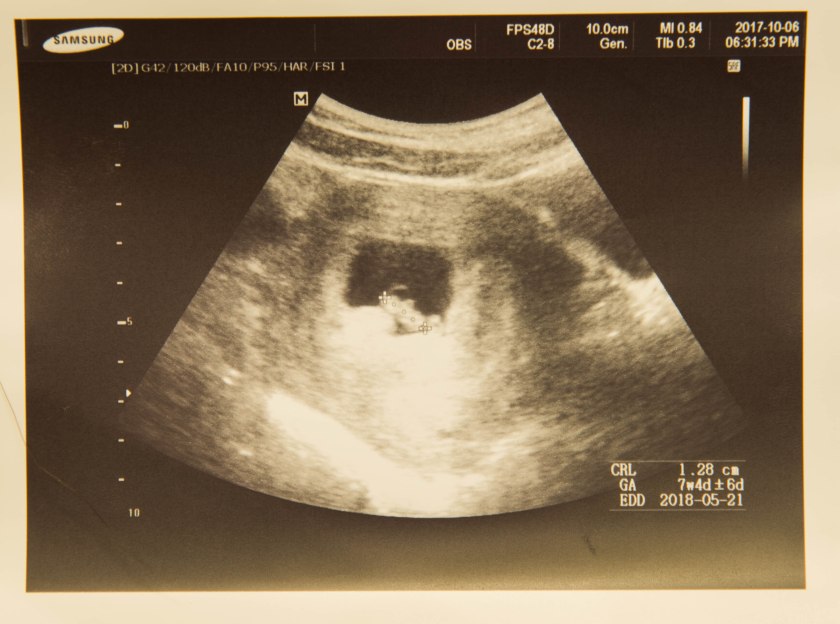

妈妈今天去了妇产科检查,医生是阿妈幼稚园多年的家长,所以对阿妈和妈妈都很好,之前都是在他这做的检查。虽然我没能一起去,但是妈妈第一时间就发了超音波照片给我。远在昆明的奶奶也收到了照片,她说看到照片感觉好幸福突然就“升级”。这真是小Puppy真正意义上的第一张照片,妈妈说陈医生还打印了两张给我们留作纪念,英国医生的小气和古板和着比起来真是相形见绌了。

这个时候的小Puppy是7周半1.28cm长,和两周前的超音波比起来已经初见人形。那时候真的只是一个圆圆的小点,我想任何一个没有经历或经验的人都不会联想到那就是一个生命的开开始吧;然而现在这张照片真的可以分辨出身体的大概轮廓。想来真是神奇,1.28cm只有一颗咖啡豆那么大,但就是那么大一个小豆豆已经开始形成自己的身体和手脚还有各种器官们。